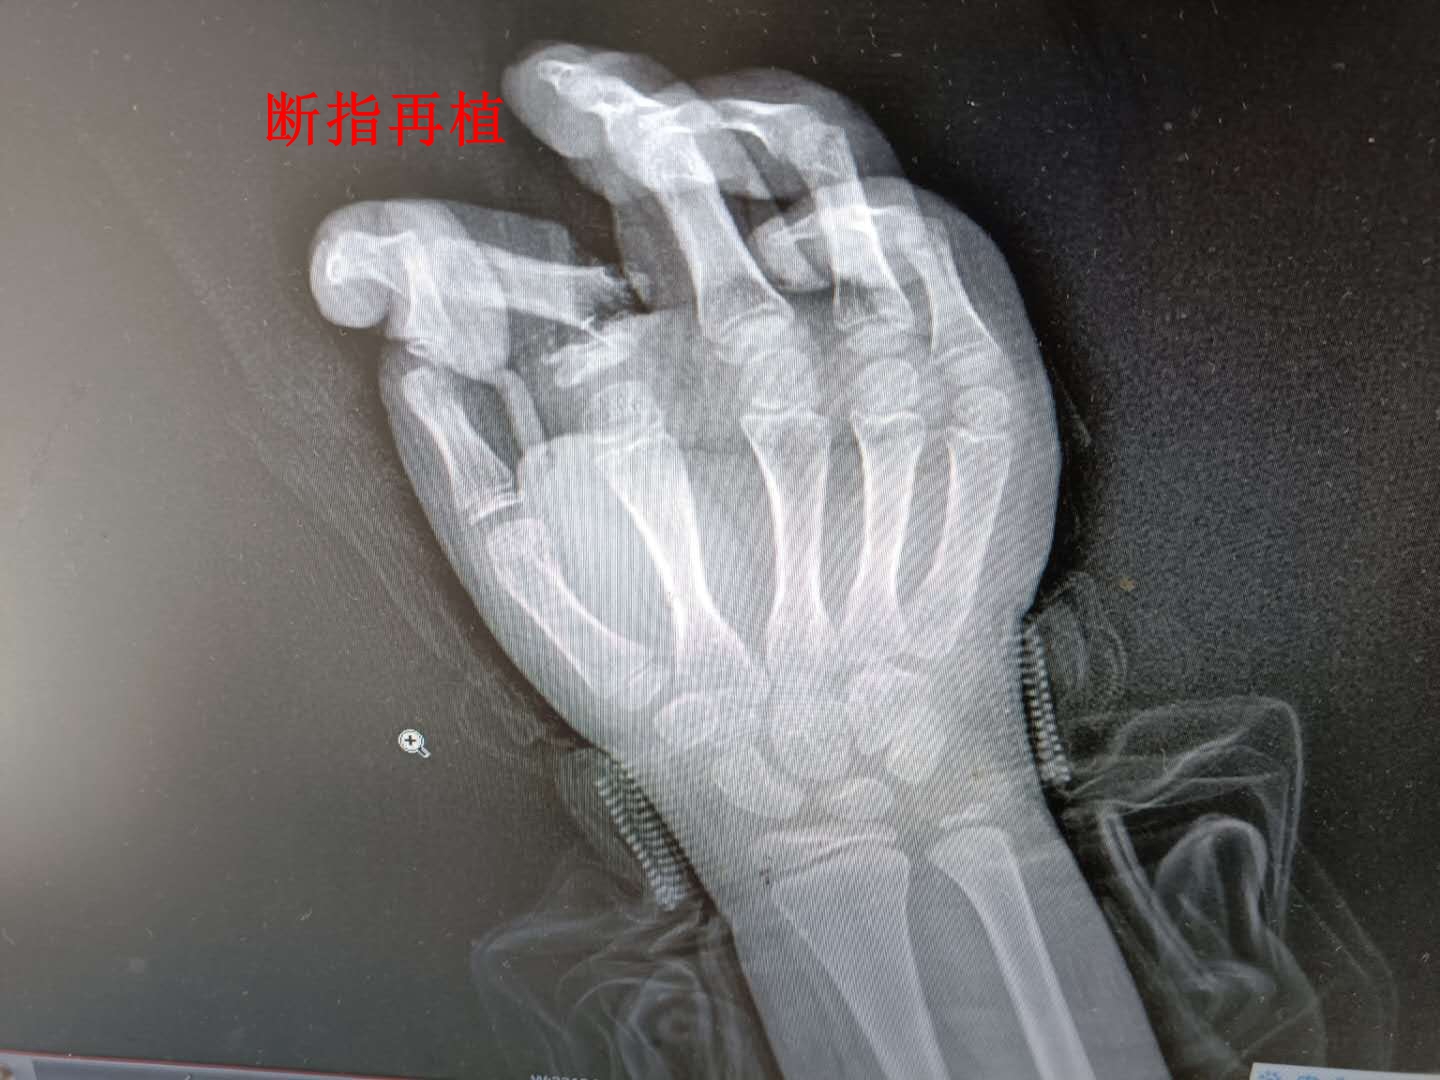

(术前X光图)

“医生,我儿子的手指被洗衣机绞断了,求求你们帮他保住啊!”3月2日下午,一阵急促的脚步伴随着呼救声打破了娄底市骨伤医院肩肘手足科病房的宁静,只见一对中年夫妻搀扶着一个10多岁的男孩,男孩的右手被纱布缠绕依旧鲜血淋漓…正在埋头书写病历的陈金强主治医师见状,连忙放下键盘。来到换药室打开纱布一看,只见其右手食指离断(旋转撕脱离断),血管神经、肌腱从断端抽出1㎝,离断指体苍白冰凉,毛细血管反应消失。情况十分危急,科主任、主任医师王胜冬会诊后决定紧急行断指再植术。